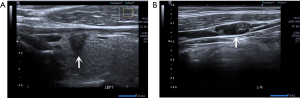

All ultrasound examinations were performed by a real-time ultrasound instrument (Aplio500, Toshiba), equipped with a 5–14 MHz transducer. The patients were asked to lie on the back with the neck fully exposed. The ultrasonographic characteristics were carefully evaluated, including Hashimoto’s thyroiditis (yes or no), multifocality (yes or no), tumor location (upper, middle, lower or isthmus), the maximum diameter (D) of tumor (D ≤10 or >10 mm), shape (irregular or regular), margin (ill-defined or well-defined), anteroposterior diameter/transverse diameter (A/T) ratio (A/T <1 or A/T ≥1), microcalcification (yes or no), intra-nodular vascularity (yes or no) and capsule invasion which meant that the shortest distance from the tumor boundary to the thyroid capsule or trachea was 0 mm (yes or no) (12).

Multivariate analysis between skip-positive group and skip-negative group

The multivariate analysis results are listed in Table 3. The upper portion [odd ratio (OR) =3.113, 95% confidence interval (CI): 0.672–14.417], D ≤10 mm (OR =3.84, 95% CI: 1.572–9.378) and capsule invasion (OR =8.07, 95% CI: 2.983–21.835) were independent risk factors for skip metastases (P<0.05) (Figure 1).